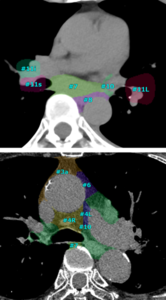

(3) リンパ節ラベル(CT)*11

リンパ節は全身に存在しており,想定外の箇所で腫大が生じる場合もあるため,その読影には大きな負担を要する。従来,「SYNAPSE SAI viewer」ではCT画像(造影・非造影)における頸部/縦隔・腋窩/腹部の腫大傾向のリンパ節の抽出が可能であったが,レポート作成時に必要なリンパ節の解剖学的名称の把握をより簡便化する機能に対する市場要望があった。今回搭載する新機能は,肺がん取扱い規約(第8版)および食道がん取扱い規約(第12版)の2つのガイドラインで定義された縦隔リンパ節区域をラベリングできる機能である。既に搭載されているリンパ節抽出機能と合わせて本機能を利用することで,解剖区域を埋め込んだスマート定型文を呼び出すことができ,レポート作成効率の向上が期待される。

肺癌取り扱い規約(第8版)によるラベリング |

食道癌取り扱い規約(第12版)によるラベリング |

リリース済みのリンパ節抽出機能と併用することで,取扱い規約に則った解剖区域を埋め込んだ所見文候補を表示可能である。